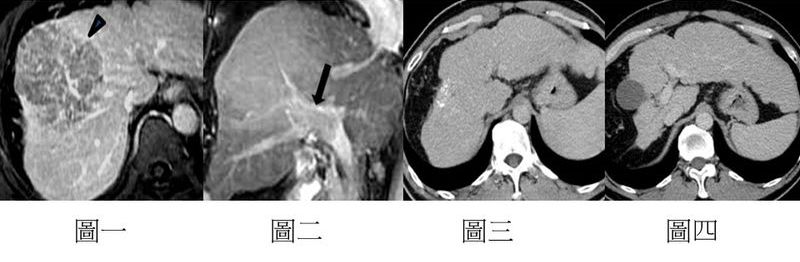

▲案例分享:40歲男性病人,原本預估只剩6個月的存活期,但是經過高榮新的HAIC治療配方(6次療程)後完全緩解(complete remission),至今存活超過14年

圖一、二:MRI可看到腫瘤(箭頭)且已侵犯到門靜脈(箭號)

圖三、四:14年的CT追蹤影像,可見腫瘤完全緩解